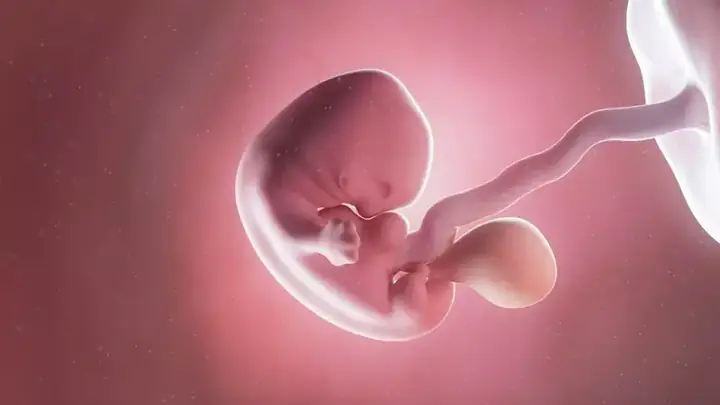

Tuần thứ 7 là một cột mốc quan trọng trong thai kỳ. Lúc này, phôi thai đã chính thức được gọi là “thai nhi” và bắt đầu có những hình dạng giống con người hơn. Các cơ quan chính như tim, não, gan, thận đều đang trong quá trình hình thành và phát triển mạnh mẽ.

Theo các chuyên gia sản khoa, kích thước phôi thai 7 tuần tuổi trung bình khoảng 10-12mm, tương đương với kích thước của một quả nho nhỏ. Đây là giai đoạn nhạy cảm khi các cơ quan nội tạng đang hoàn thiện, vì vậy mẹ bầu cần đặc biệt chú ý đến chế độ dinh dưỡng và sinh hoạt.

Trong tuần thai thứ 7, thai nhi đang trải qua những thay đổi đáng kinh ngạc. Tim thai đã bắt đầu đập với nhịp khoảng 100-160 lần/phút, gấp đôi nhịp tim của người lớn. Các cấu trúc cơ bản của não bộ cũng đang được hình thành, cùng với đó là sự phát triển của các dây thần kinh.

Hệ tiêu hóa cũng đang trong quá trình phát triển với sự hình thành của thực quản, dạ dày và ruột non. Gan bắt đầu sản xuất tế bào máu, còn thận thì bắt đầu thực hiện chức năng lọc máu. Đây là những dấu hiệu cho thấy thai nhi đang phát triển khỏe mạnh và bình thường.